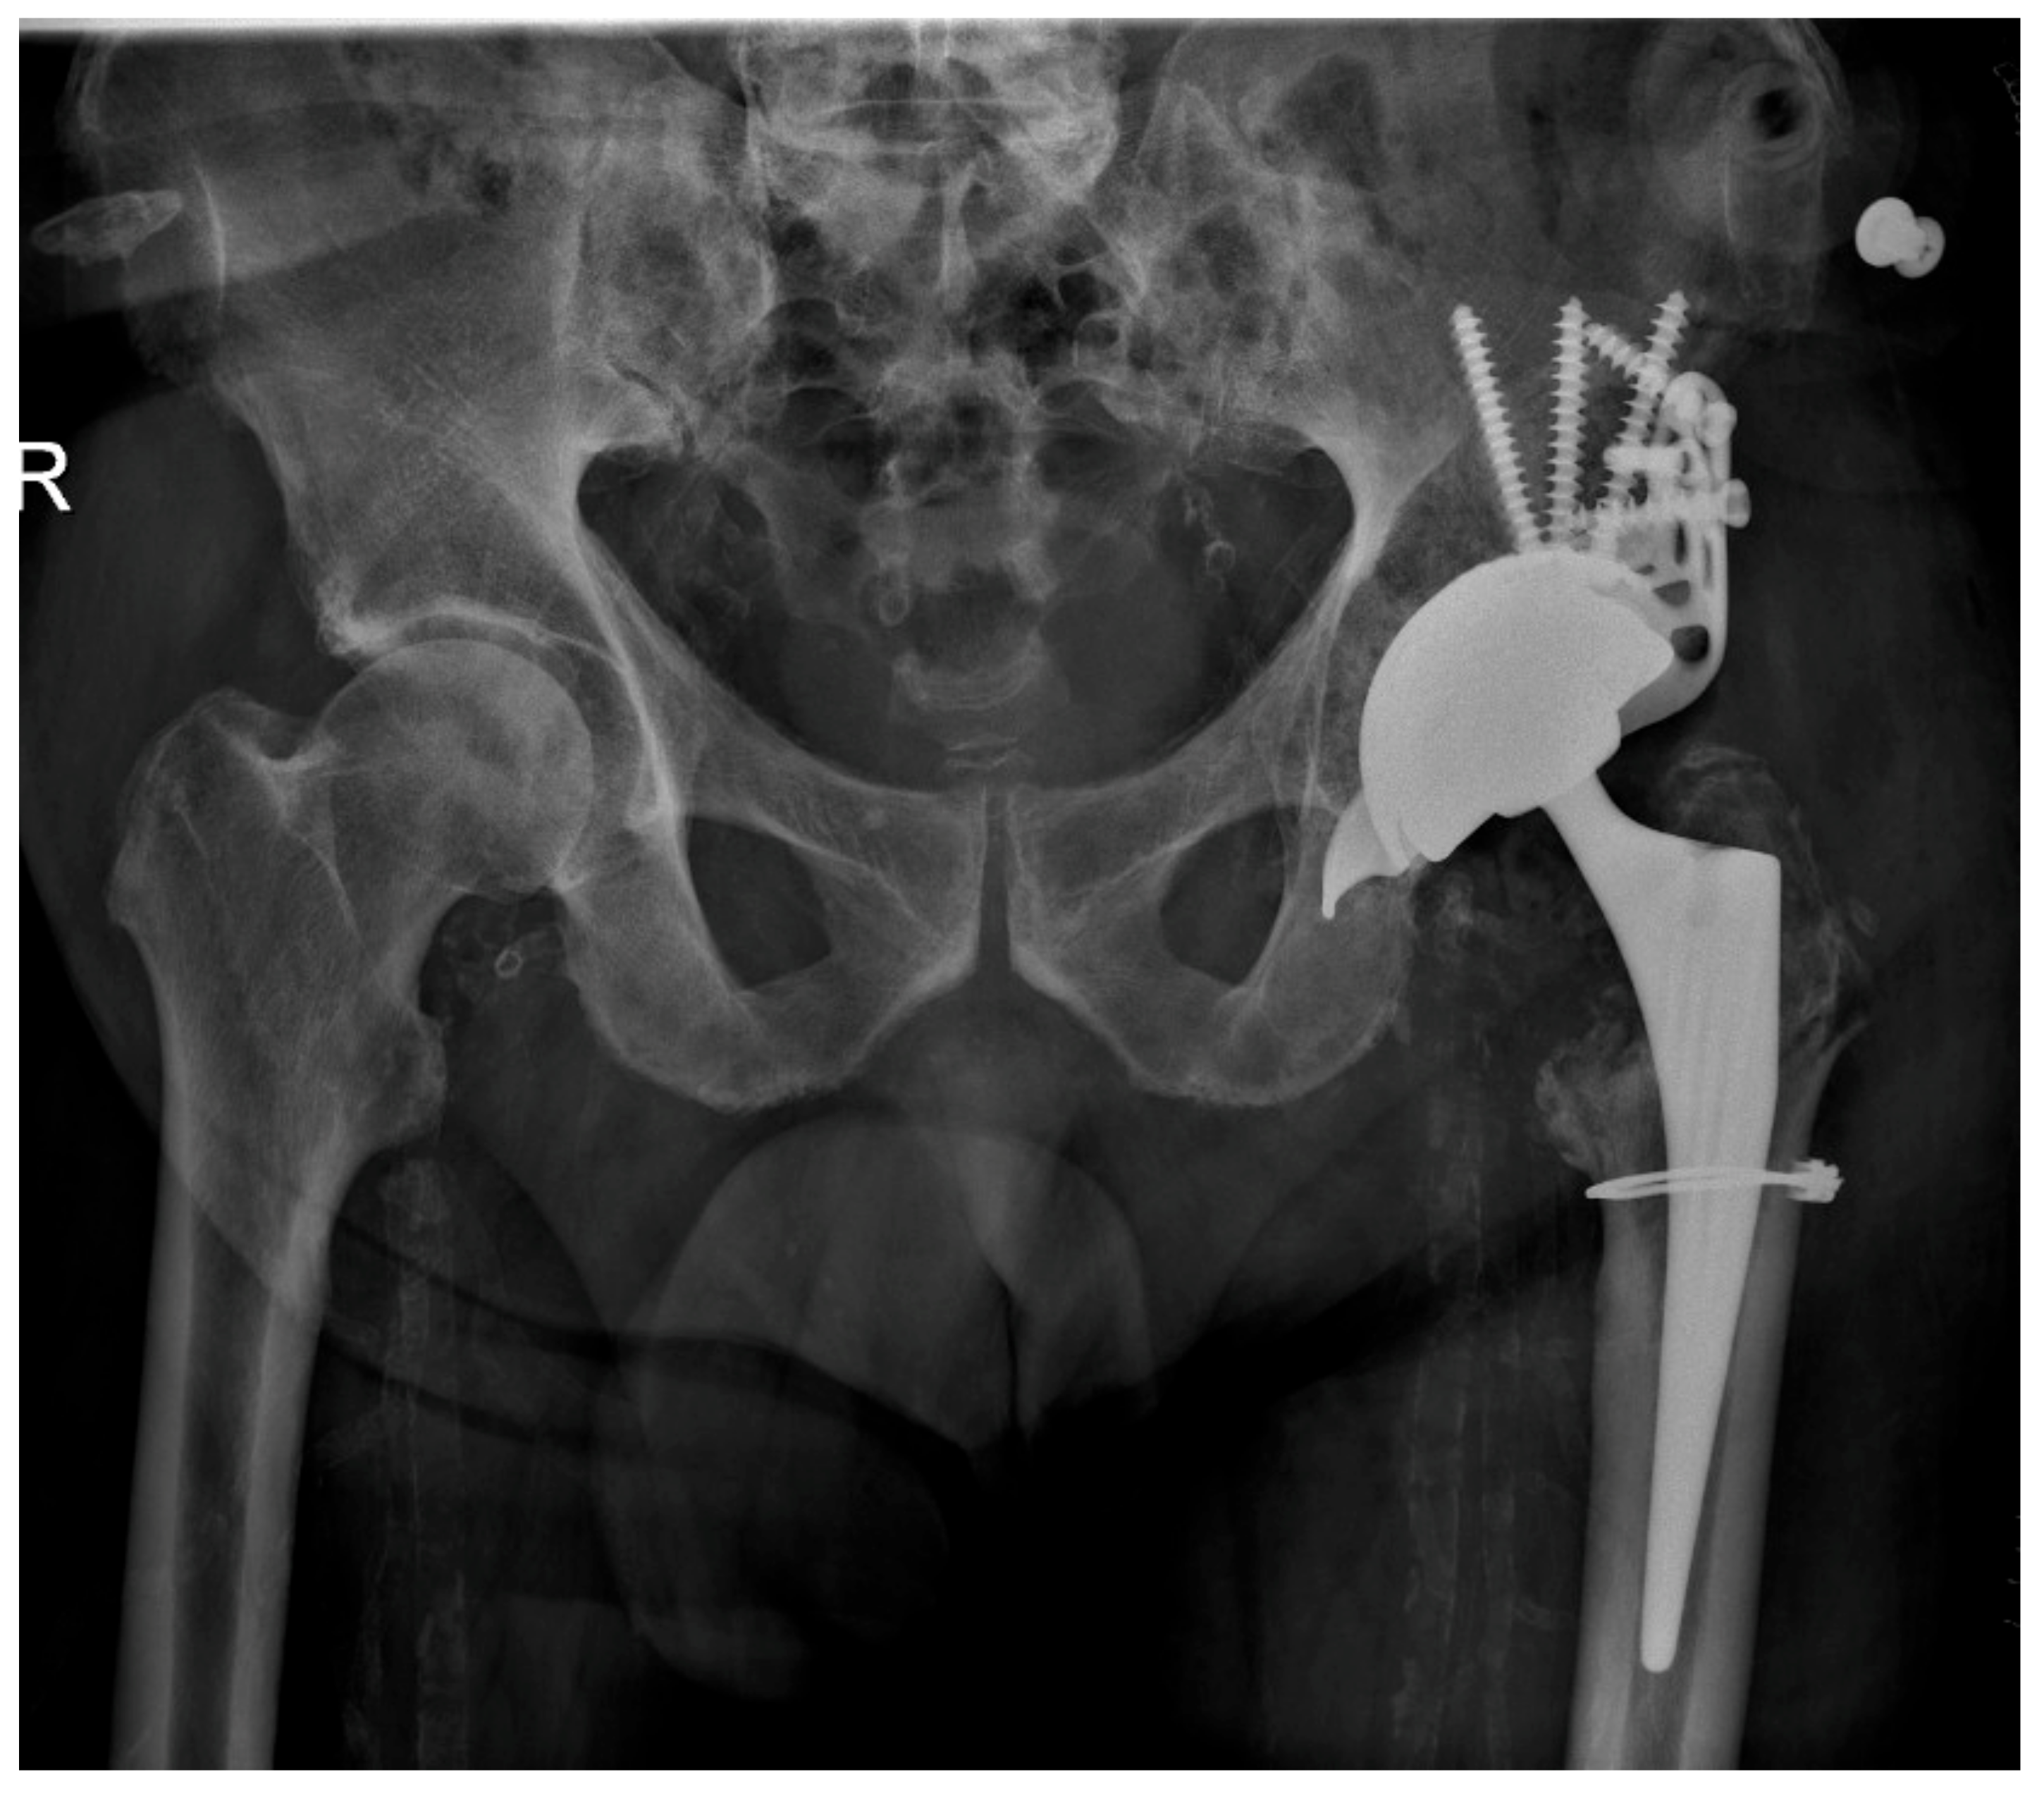

Figure 6. Postoperative result after implantation of a Burch Schneider reinforcement cage (diameter 56 mm). The periprosthetic fracture of the femur (Vancouver A2) was fixed with a cerclage wire.